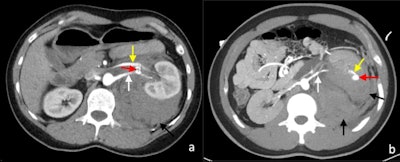

Postcontrast arterial phase axial CT images of vascular complications following nontargeted ultrasound-guided 14-gauge core biopsies of the left kidney in two patients. (A) Arteriovenous fistula. There is a fistulous connection (red arrow) between the left renal artery (white arrow) and the left renal vein (yellow) with associated early arterialised enhancement of the proximal left renal vein, medial to the arteriovenous fistula. There is an associated retroperitoneal hematoma (black arrow). (B) Arterial pseudoaneurysm. A small pseudoaneurysm (red arrow) arising from a segmental branch of the left renal artery (yellow arrow) is visualized as an adjacent small focus of rounded arterial enhancement (red arrow). The main left renal artery is also visible (white arrow). There is an associated left perinephric and retroperitoneal hematoma (black arrows).

Postcontrast arterial phase axial CT images of vascular complications following nontargeted ultrasound-guided 14-gauge core biopsies of the left kidney in two patients. (A) Arteriovenous fistula. There is a fistulous connection (red arrow) between the left renal artery (white arrow) and the left renal vein (yellow) with associated early arterialised enhancement of the proximal left renal vein, medial to the arteriovenous fistula. There is an associated retroperitoneal hematoma (black arrow). (B) Arterial pseudoaneurysm. A small pseudoaneurysm (red arrow) arising from a segmental branch of the left renal artery (yellow arrow) is visualized as an adjacent small focus of rounded arterial enhancement (red arrow). The main left renal artery is also visible (white arrow). There is an associated left perinephric and retroperitoneal hematoma (black arrows).Follow-up ultrasound Doppler shows that over 95% of fistulae detected were asymptomatic and about 95% of the fistulae spontaneously resolved at three months after biopsy. A small number of the patients develop hemodynamically significant bleeding and require treatment. Arteriovenous fistulas lead to early arterial enhancement of the involved vein, with similar enhancement to that of the abdominal aorta and renal arteries.